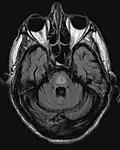

El antecedente de haber sufrido hiponatremia, sumado a las características clínicas previamente descritas son el sello de la enfermedad. La resonancia magnética puede mostrar ciertos cambios a nivel del parénquima cerebral, como es el aumento en la intensidad a nivel pontina[4]